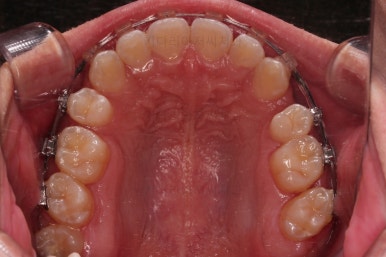

순차적으로 장치를 붙여가며 치아를 가지런하게 합니다.

가지런하게 하는 단계를 거친 뒤,당기기 과정에 들어가는데요.

이 과정에서 입이 들어가는 양, 중앙선, 기울기, 앞니 각도 등등 많은 것을 신경써서 당기기를 해주는데요.

이 때 필요한 것이 미니스크류 입니다.

예전과는 다르게 미니스크류를 이용해서 좀 더 정교하고 고난이도의 치료가 가능해지게 된거죠.